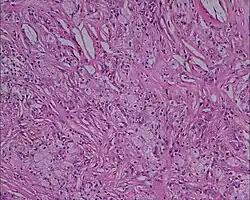

Xanthome (von altgriechisch ξανθός (xanthos) = gelb) sind an sich harmlose, orange-gelblich schimmernde, knoten- bis plaqueartige Fettablagerungen in der Haut. Sie werden auch als Gelbknoten bezeichnet. Sie sind lokalisierte Ansammlungen von Makrophagen, die massenhaft Fette eingelagert haben und sich zu Schaumzellen umformen. Xanthome entstehen durch Fettstoffwechselstörungen, überwiegend bei erhöhtem Cholesterinspiegel. Auch Erkrankungen mit Ursachen in anderen Stoffwechselwegen können als Ursache bei Xanthomen vorliegen. Solche Erkrankungen werden als Xanthomatosen bezeichnet. Ein Beispiel dafür ist die cerebrotendinöse Xanthomatose, eine seltene neurodegenerative Erkrankung bei Störung des Gallensäure-Stoffwechsels.[1][2]